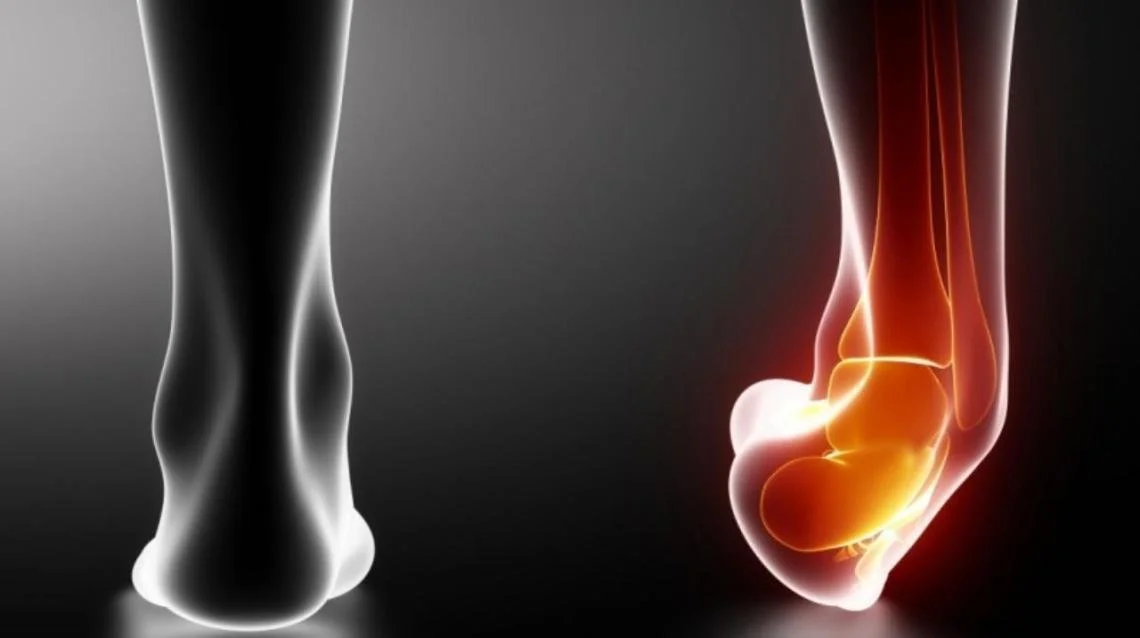

We strive to restore your foot & ankle function using the the least invasive treatment possible so you can get back to on your feet. Dr. Henry uses both nonoperative treatments and surgeries to get you back to doing what you love. These are just some of the procedures Dr. Henry specializes in.

Through a joint decision-making process, we may recommend surgical treatment if we believe the potential benefits outweigh the risks. For patients with chronic (long-term) conditions, the decision for surgery may come after a period of nonoperative treatment, including shoewear changes, orthotics (shoe inserts), ankle/foot braces, physical therapy, medication, activity optimization, and injections. You will discuss this in your consultation with Dr. Henry.